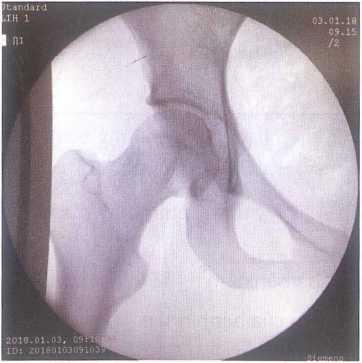

Người nắn cẩm ở khoeo chân, kéo chân xuống phía dưới nhẹ nhàng, sau đó, bắt đẩu nâng nhẹ nhàng chân lên đến 70 độ và tăng lực kéo chân xuống phía dưới, có thể lắc nhẹ chân để tạo thuận lợi cho chỏm xương đùi vào ổ cối. Một tiếng kêu “clunk” là dấu hiệu chỏm xương đùi đã vào ổ cối, kiểm tra lại bằng cách vận động khớp háng các tư thế. Có thể kiểm tra lại bằng máy C-arm ngay tại phòng mổ.

Hình 3.13. Hình ảnh kiểm tra trên C.arm sau nắn trật khớp háng